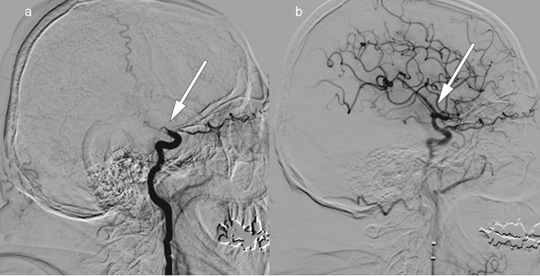

Patient 2. A woman in her 70s experienced acute onset of right-sided paralysis, dizziness and dysarthria after heart surgery. Her NIHSS score was 23 points (severe cerebral infarction). Intravenous thrombolytic therapy was contraindicated. The image to the right shows cerebral angiography with contrast injection in the left vertebral artery, c) before and d) after embolectomy of a large thrombus (arrows) with occlusion of the superior cerebellar artery, posterior cerebral artery and the bifurcation of the basilar artery. Embolectomy was performed with recanalisation 220 minutes after symptom onset. The event presumably occurred after heart surgery. Further workup also revealed atrial fibrillation. The patient received anticoagulation therapy with warfarin, and at follow-up three months later, the NIHSS score was 0 points.